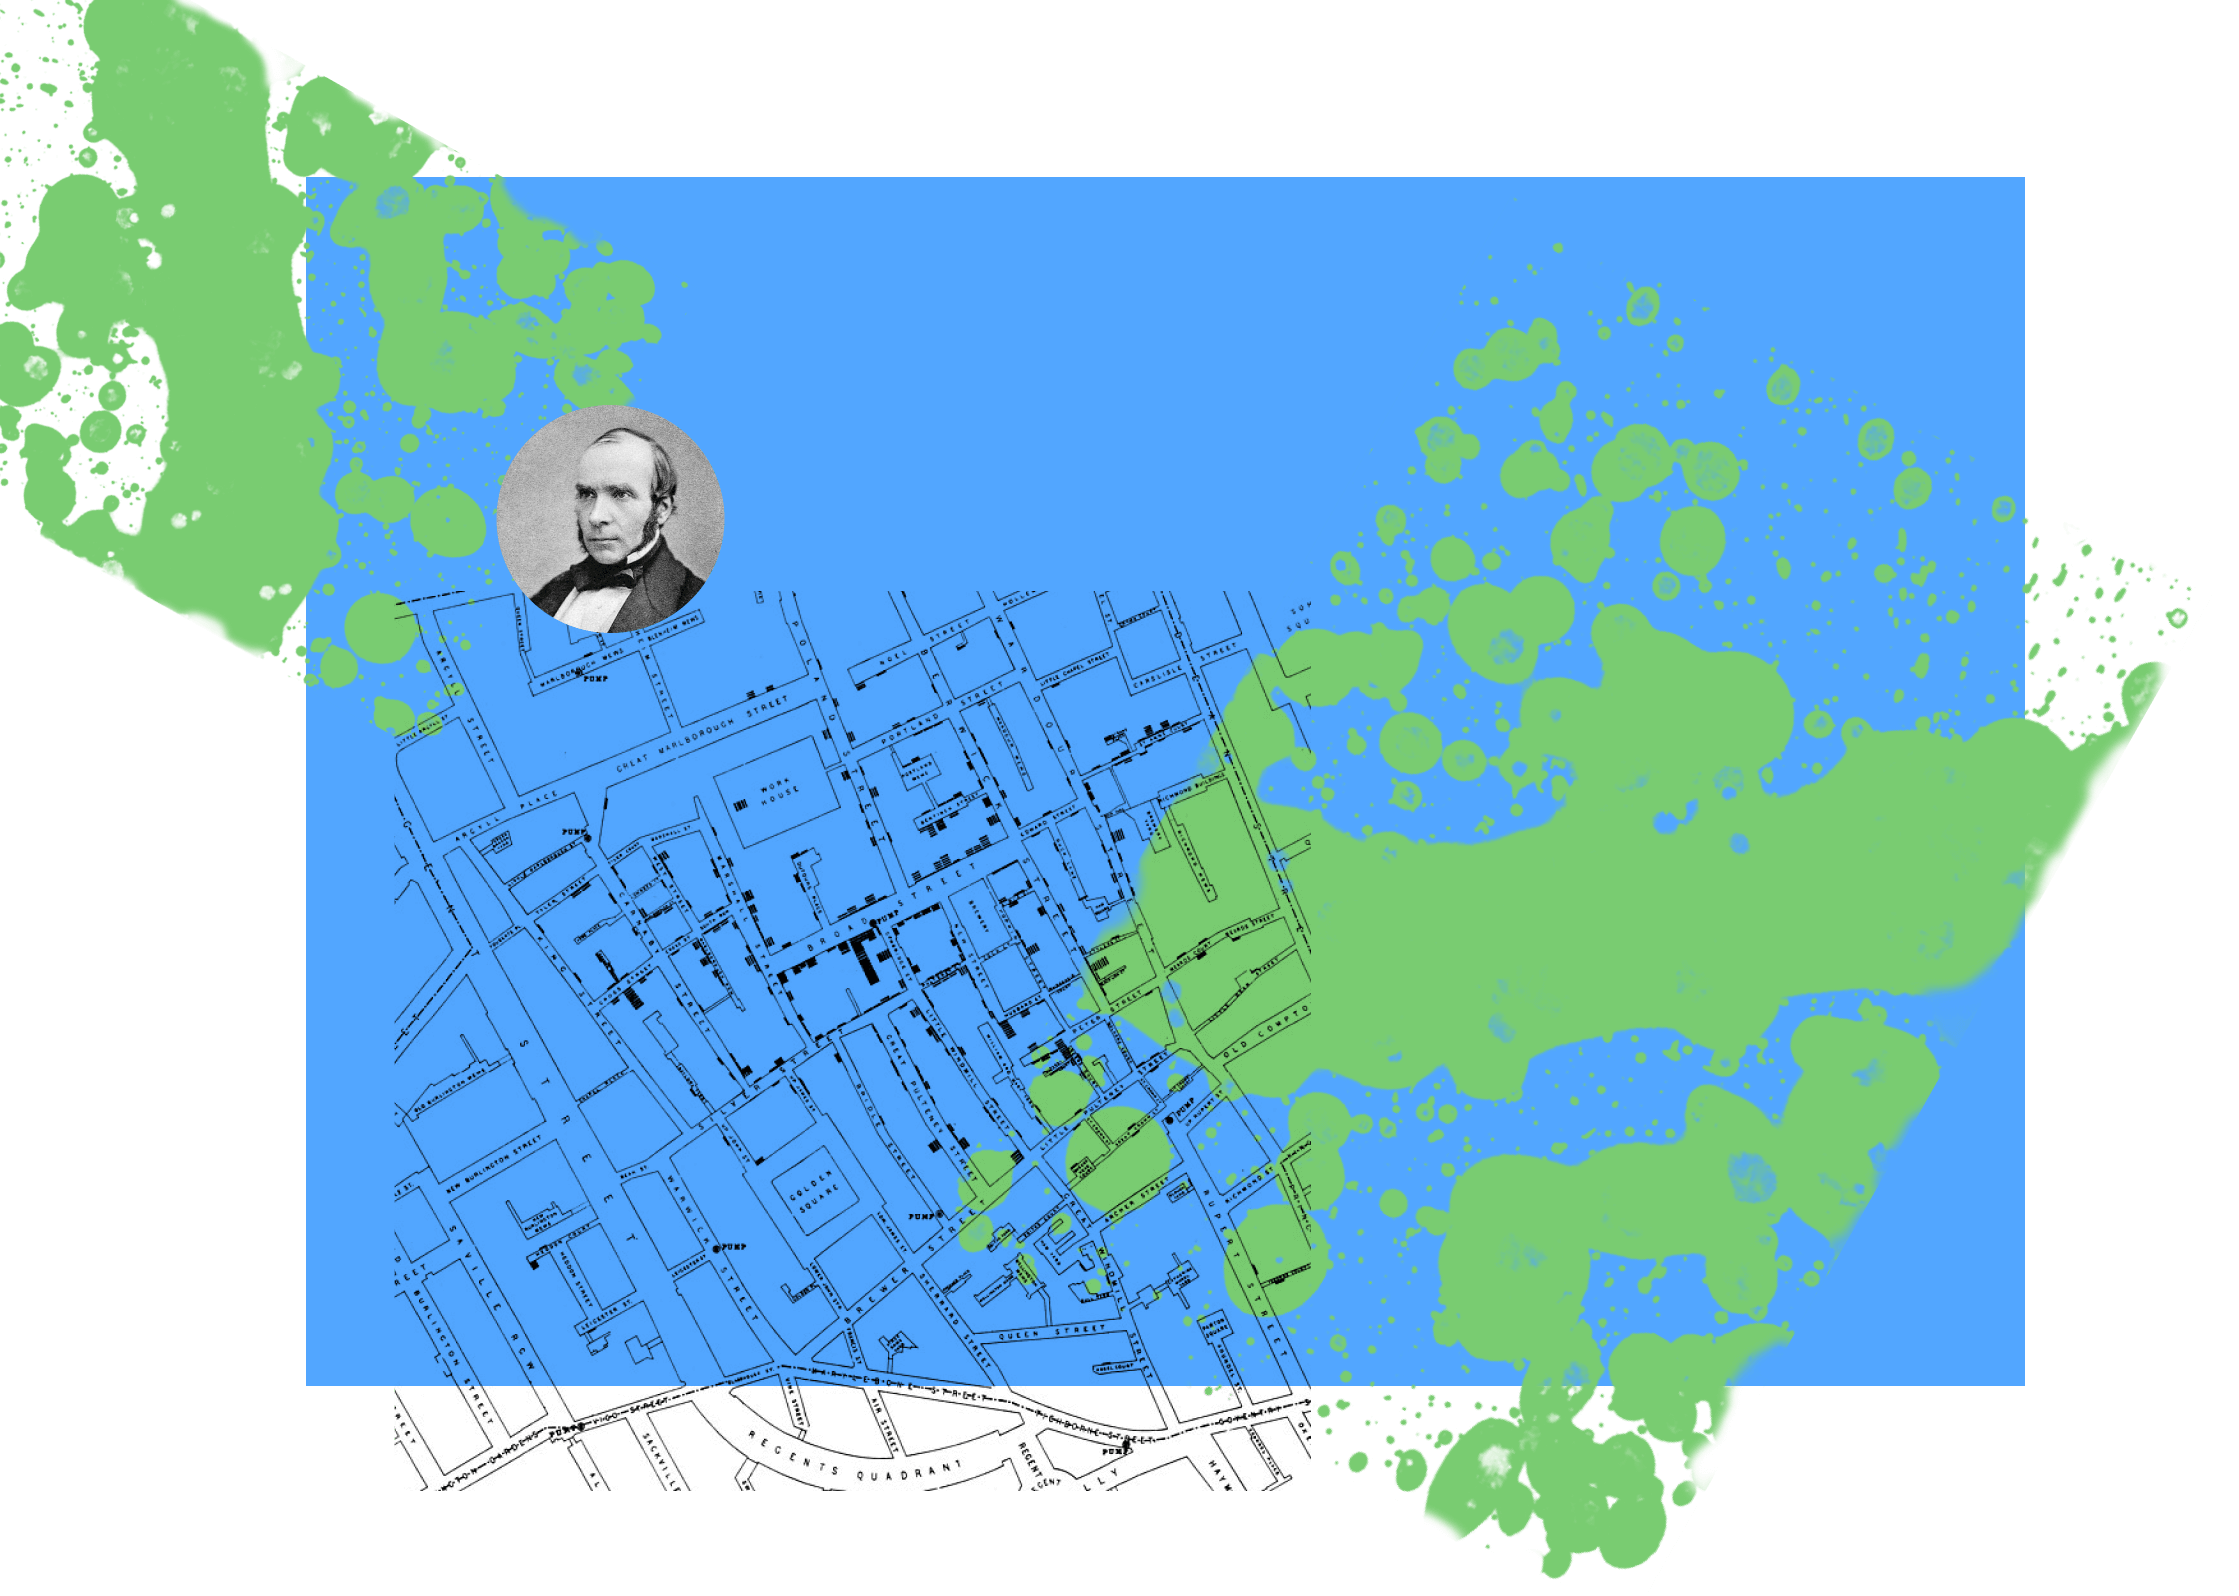

Вспышки холеры уносили в разных странах по миллиону человек

третья эпидемия холеры

Вспышка холеры в 1854 году унесла жизни 616 человек. Наиболее известна благодаря врачу Джону Сноу и его доказательству о том, что источником холеры была зараженная микробами вода.

Для дизайнеров это особо важный случай, т.к гипотеза была доказана благодаря инфографике. Джон Сноу нарисовал карту с обозначением плотности заболевших и расположением колонок воды.

Джон Сноу

(не король Севера)

и его карта

(не король Севера)

и его карта